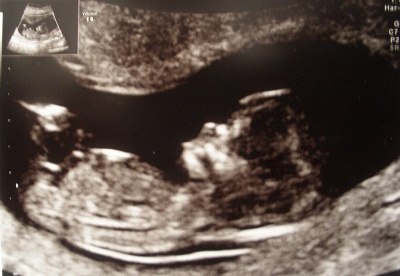

Nå, men det gik VIRKELIG godt! Det første hun sagde var, at hjertet slog. Og så scannede hun løs! Vi har dog en lille bølle derinde, for hun havde virkelig svært ved at finde de rette positioner, fordi den sprællede hele tiden og vendte og drejede sig, og hun måtte flere gange give sig til at grine opgivende, fordi den bare ikke ville ligge sig pænt! Hehe

Vi så både arme, ben, og en hånd med alle 5 fingre. Alt er normalt! Navlestrengen så normal ud, kraniet så normalt ud, alt var perfekt.

Nu skal jeg nok prøve at tage den lidt med ro fremover! Jeg nød at det var svært for hende at scanne, for så kunne vi jo nyde den lille lidt længere. Det var en stor oplevelse, især da hun afspillede dens hjerteslag. Dens hjerte slår med 165 slag i minuttet, og det skulle ligge mellem 150-170, så det er perfekt!

Her er lige et par fotos af lille blypper!